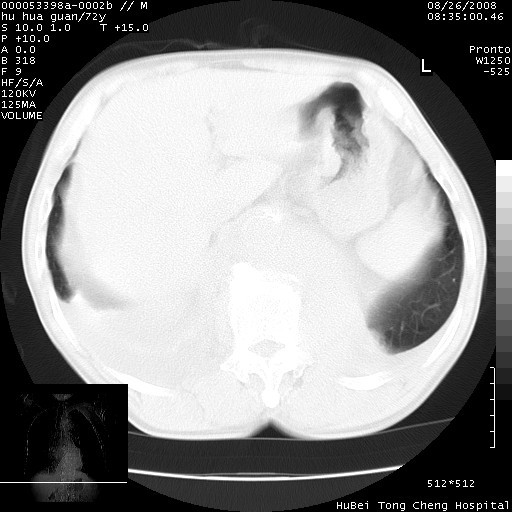

可以明确的说。肯定不是主动脉夹层破裂出血!考虑为淋巴瘤或间叶组织来源的恶性肿瘤可能性大。右肺小结节建议薄层观察,如能发现恶性征象,那椎前改变就考虑为转移所致。至于双侧少量胸水乃静脉血回流受阻所致。

图像及窗宽窗位均不理想。周围性肺癌/胸腔积液/纵隔积液。

1、右肺周围性肺癌、胸腔积液(双)

2、建议食道吞钡和增强检查排除食道和主动脉病变

3、后纵隔淋巴类肿瘤

1、右上肺结节病变,肺泡癌不除外,请随诊;左下肺近后纵隔病变,考虑纵隔型肺癌侵犯大血管可能;

2、右下肺背段少许炎症,双侧胸腔积液,右下肺纤维索条。

降主动脉前移位,后纵隔占位

后纵隔占位,降主动脉前移位;双侧胸腔积液;应排外食管病变侵犯血管可能;